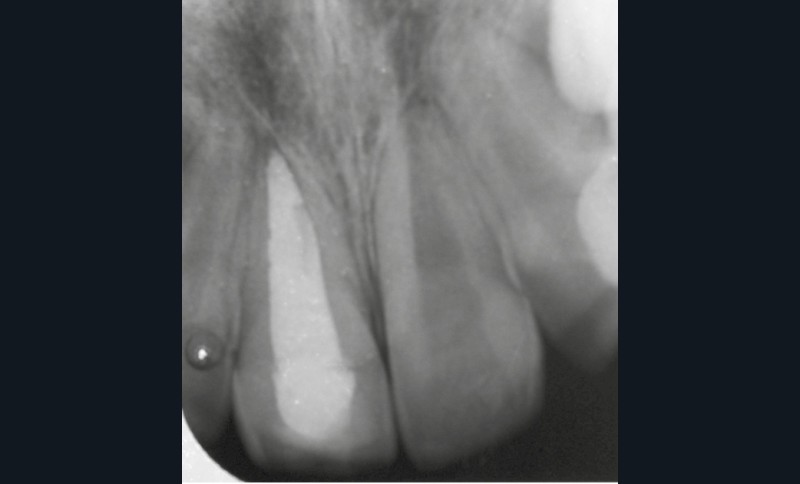

Enfant de 9 ans dont une incisive centrale maxillaire a été expulsée en jouant au football. Appel immédiat de la mère à qui l’on conseille de conserver la dent expulsée dans du sérum physiologique (fig. 1). Le temps extra-alvéolaire à sec a été inférieur à 5 minutes. Le patient arrive 40 minutes après le traumatisme dans l’Unité d’Odontologie pédiatrique. Après interrogatoire, examen clinique et radiographique, un rinçage de l’alvéole est effectué et la dent est réimplantée le plus rapidement possible (fig. 2). Une contention semi-rigide est ensuite placée (fig. 2). La dent étant mature, la prise en charge endodontique (séance de Ca(OH)2 puis obturation à la gutta percha) débute deux semaines plus tard (fig. 3 et 4) afin de limiter les risques d’infection, de résorption. Le suivi sur quatre années montre une dent fonctionnelle, sans ankylose ni résorption radiculaire ou osseuse.